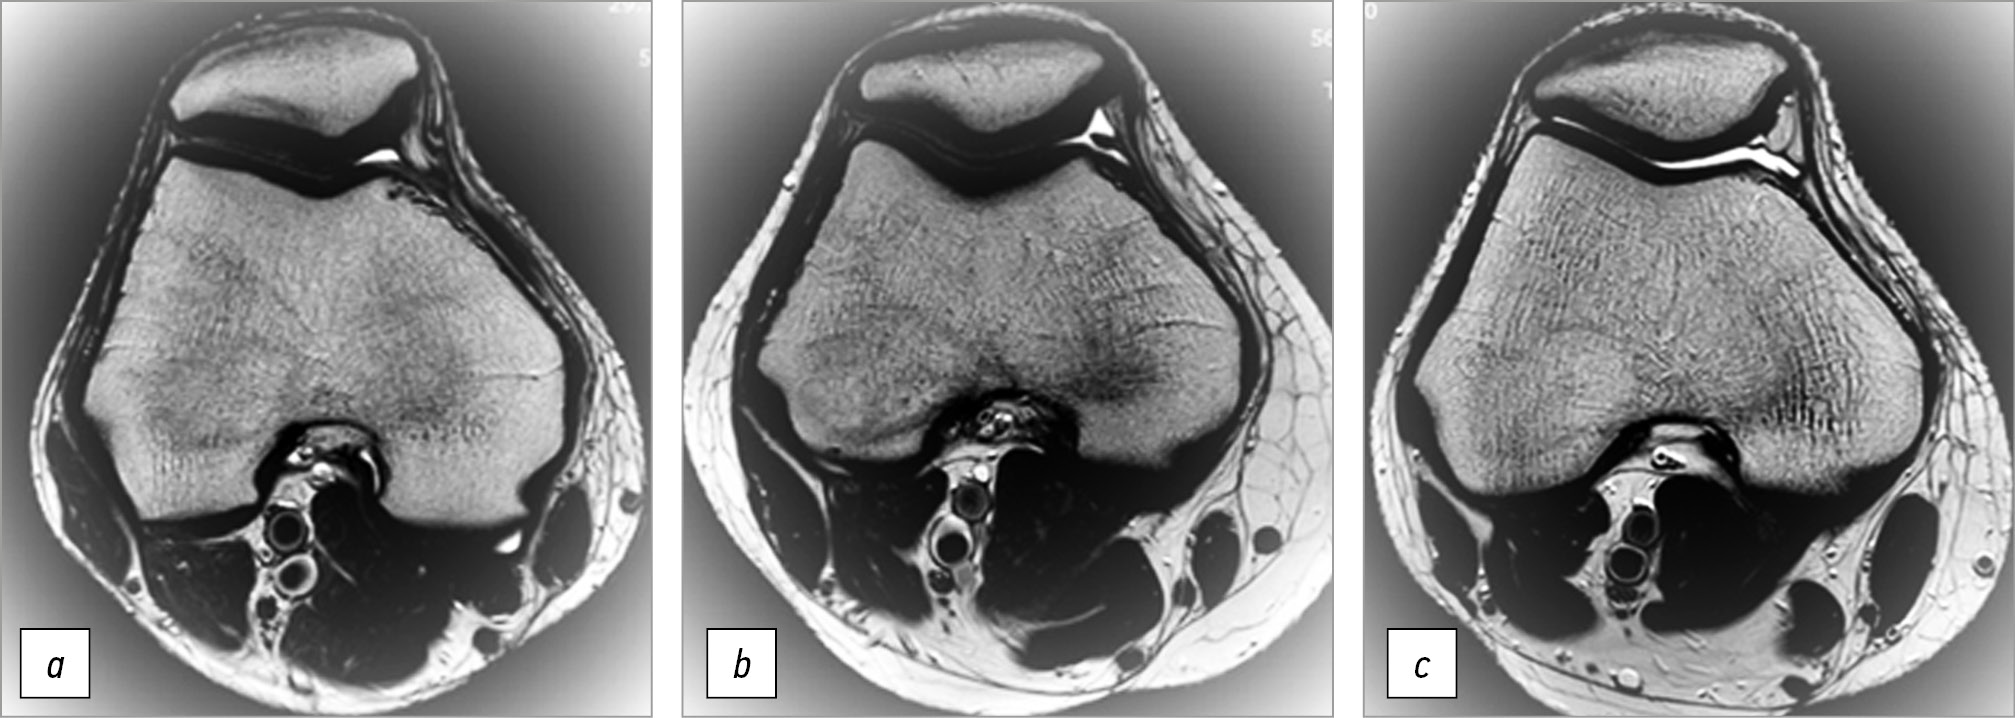

Для изучения степени патологического утолщения МПСС используется классификация J.O. Sakakibara [12]:

- тип А — складка представлена линейным жгутооб- разным утолщением синовиальной стенки по медиальной поверхности капсулы сустава (рис. 1, а);

- тип B — складка представлена удлиненным линейным тяжом с неровными контурами, но не достигает медиального мыщелка бедренной кости (рис. 1, b);

- тип С — складка удлинена, утолщена, с неровными бахромчатыми контурами, распространяется на область медиального мыщелка бедренной кости (рис. 1, c);

Рис. 1. На жировой клетчатке подавлены осевые разрезы Т2ВИ, проходящие от центра надколенника на 3 см выше суставной щели. Определяется медиопателлярная синовиальная складка: а — тип A в сочетании с дисплазией мыщелка бедренной кости типа А; b — тип B в сочетании с дисплазией мыщелка бедренной кости типа В, наличие синовита увеличивает обзорную видимость медиопателлярной синовиальной складки; c — тип B в сочетании с дисплазией мыщелка бедренной кости типа С

Fig. 1. On the fatty tissue, axial T2VI incisions are suppressed, extending from the center of the patella 3 cm above the joint space. The mediopatellar synovial fold is determined: a — type A in combination with type A femoral condyle dysplasia; b — type B in combination with type B femoral condyle dysplasia, synovitis increases the visibility of the mediopatellar synovial fold; c — type B in combination with type C femoral condyle dysplasia